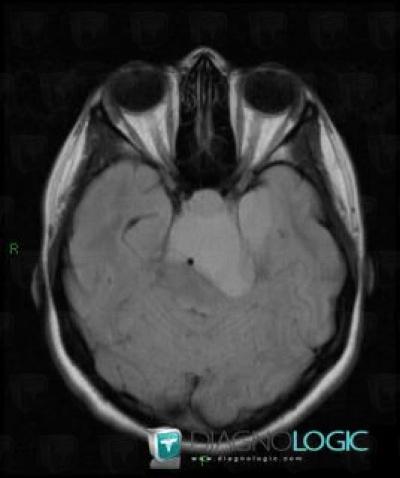

Craniopharyngiome, Angle ponto cérébelleux, IRM

Voici les informations spécifiques à l'image clé ci dessus:

- Diagnostic Craniopharyngiome, Localisation(s) Angle ponto cérébelleux, comportant les gammes Masse de l'angle ponto cérébelleux